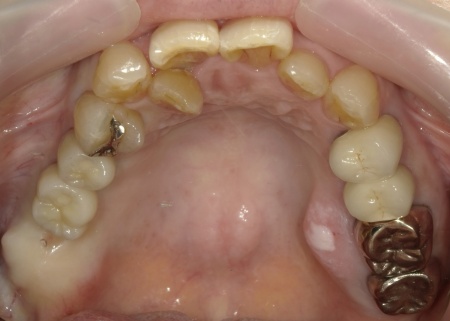

拝見したところ、右上の歯には、欠損部位前後の歯を土台として橋を渡すように連結した被せ物「ブリッジ」が装着されていました。

しかし、土台となっている手前の歯(第2小臼歯)は歯根が割れており、同じく土台となっている奥の歯(第2大臼歯)は歯根の先に膿の袋ができる「根尖病巣(こんせんびょうそう)」が認められます。

さらに、ブリッジ部位の歯茎は腫れ、痛みもあるとのことでした。